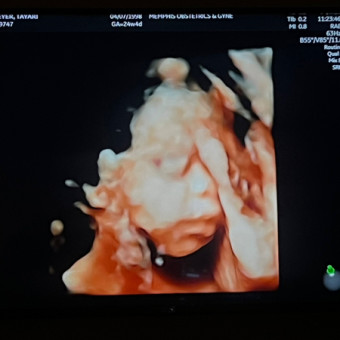

Tayari & Chris Meyer Registry

Tayari & Christopher Meyer

Cordova, TN

August 14, 2025

We can't wait to meet our little boy earth bound ❤️ we thank you for your love and support ❤️